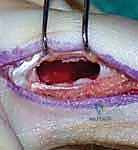

Exposure and Cortical Window Creation

The surgical approach is executed precisely as templated, utilizing the appropriate internervous and intermuscular planes. Once the periosteum overlying the lesion is exposed, it is carefully incised longitudinally and elevated. The creation of the cortical window is a critical step; it must be large enough to allow complete visualization of the entire tumor cavity, including all hidden recesses, yet designed to minimize structural weakening of the bone. For tubular bones, an oblong or elliptical window is fashioned using a high-speed burr or fine osteotomes, avoiding sharp corners that act as stress risers. The cortical lid can occasionally be preserved in saline and replaced at the conclusion of the procedure, acting as a biological barrier to contain the graft or cement.

Extended Intralesional Curettage

The core of the procedure for benign and locally aggressive tumors is extended intralesional curettage. Gross tumor is initially removed using a series of progressively sized curettes. It is imperative to systematically scrape the endosteal surface in multiple directions to eradicate all visible neoplastic tissue. However, simple curettage alone leaves microscopic disease within the cancellous bone interstices, leading to unacceptable recurrence rates (historically up to 40-50% for GCTs). Therefore, the procedure must be "extended" using a high-speed spherical burr. The burr is utilized to aggressively abrade the cavity walls, expanding the margin by 1 to 2 millimeters into normal-appearing, bleeding cancellous bone. Continuous pulsatile lavage is employed during burring to clear debris and prevent thermal necrosis of the adjacent articular cartilage.